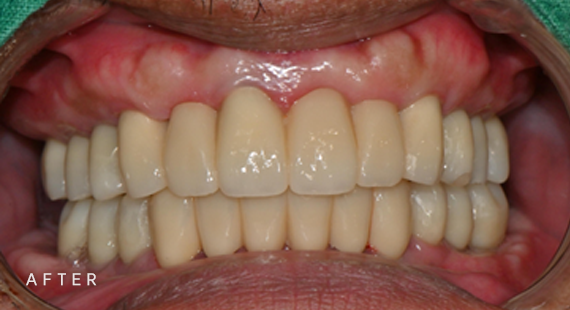

임플란트